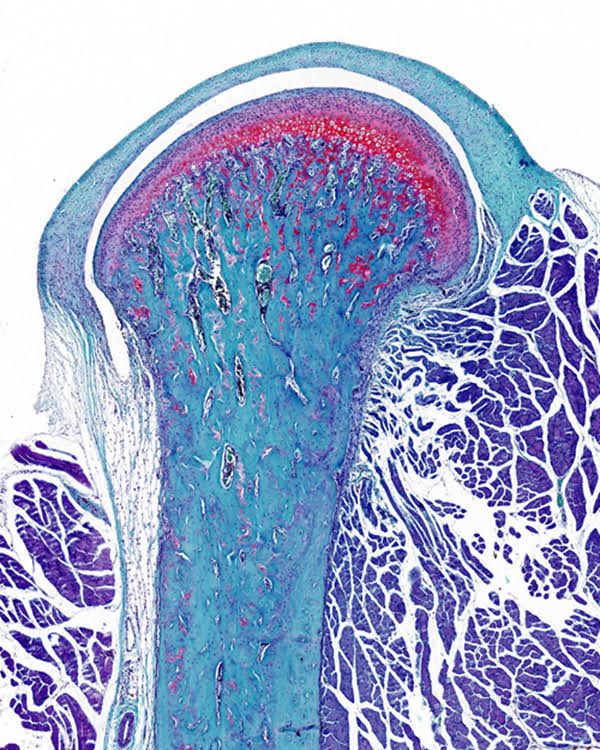

為促進科學(xué)文化發(fā)展,活躍專委會的科技人文氛圍,培養(yǎng)科研工作者的創(chuàng)新意識,激發(fā)他們發(fā)現(xiàn)美、創(chuàng)造美的熱情和興趣,本次年會特別增加了一項“生命的藝術(shù)——首屆年度顯微圖片展”活動。在專委會發(fā)出征稿通知之后,來自全國近20 所院校的師生積極響應(yīng),共投稿顯微攝影作品125 幅。經(jīng)以王松靈院士為主席的九位審讀專家組成員在線上線下的認真審閱和討論,從圖片的原創(chuàng)性、科學(xué)性和藝術(shù)性三個方面進行綜合考量,最終確定年度圖片1 幅,年度提名圖片20 幅。在此匯集成冊,與各位同仁分享、交流。

這些作品幾乎均為創(chuàng)作者在日??蒲泄ぷ髦幸圆煌募夹g(shù)手段捕捉到的微觀生命瞬間,科學(xué)的“透鏡”似乎為我們展現(xiàn)出一幅幅藝術(shù)的“魔幻”,一邊是細胞、分子層面的微觀抵達,另一邊好似一塊既陌生又熟悉的“優(yōu)詩美地”。這里,本是科學(xué)嚴謹?shù)念I(lǐng)地,因為其關(guān)乎生靈,便開啟人們自由逸放的審美思緒。在此,我們驚嘆中國古代哲學(xué)體系中“天人合一、道法自然”的天道規(guī)律。原來早于現(xiàn)代科學(xué),這種“盡精微而致廣大”的宇宙觀便已根植于我們生存的大地。感謝各位作者以他們現(xiàn)代技術(shù)的視野,為我們定格生命律動的瞬間,張揚蓬勃的藝術(shù)活力。換一個視角,生命的風景便呈現(xiàn)“天地人”的和諧和統(tǒng)一,換一種思路,生命的哲學(xué)便更能詮釋苦難與幸福的非凡境遇。